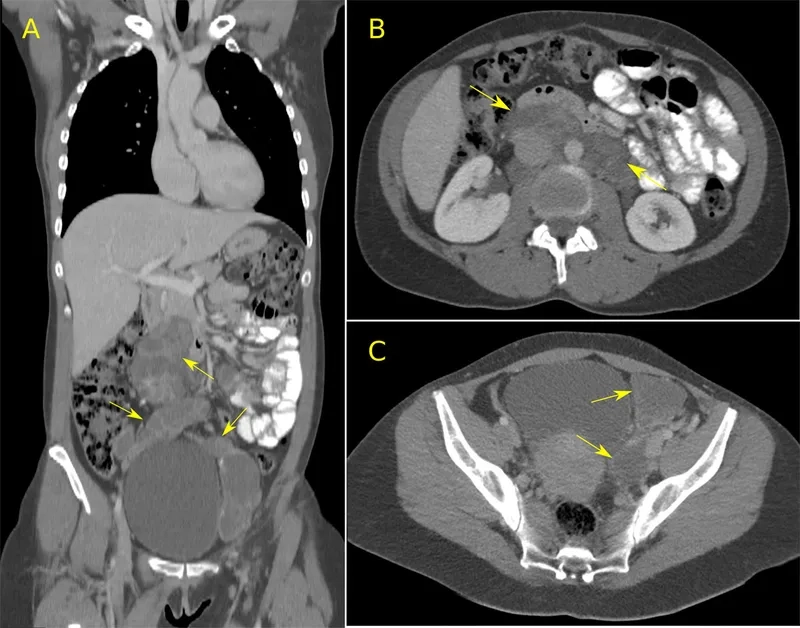

• Other potential signs include benign kidney tumors (angiomyolipomas), a persistent cough, chest pain, and fatigue, which can impact daily quality of life.

Image of the disease Lymphangioleiomyomatosis

Tuberous sclerosis complex medical chart